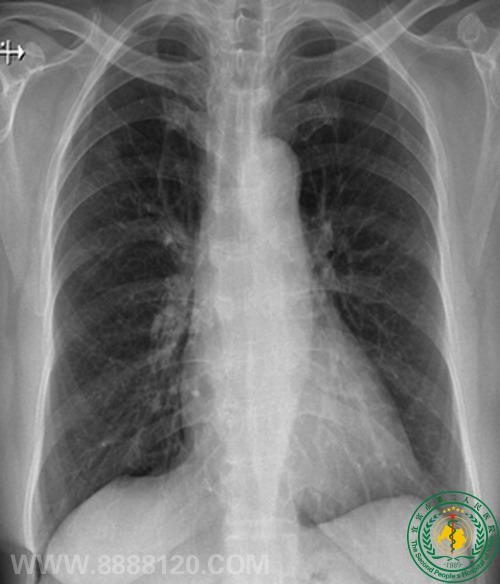

病例75病员诉胸闷,无胸痛。

DR示双侧胸膜钙化,CT示右肺下叶背段磨玻璃密度结节,疑为肺Ca,不完全除外感染性病变。肺穿刺少许组织送病检:结果为肺泡细胞癌。